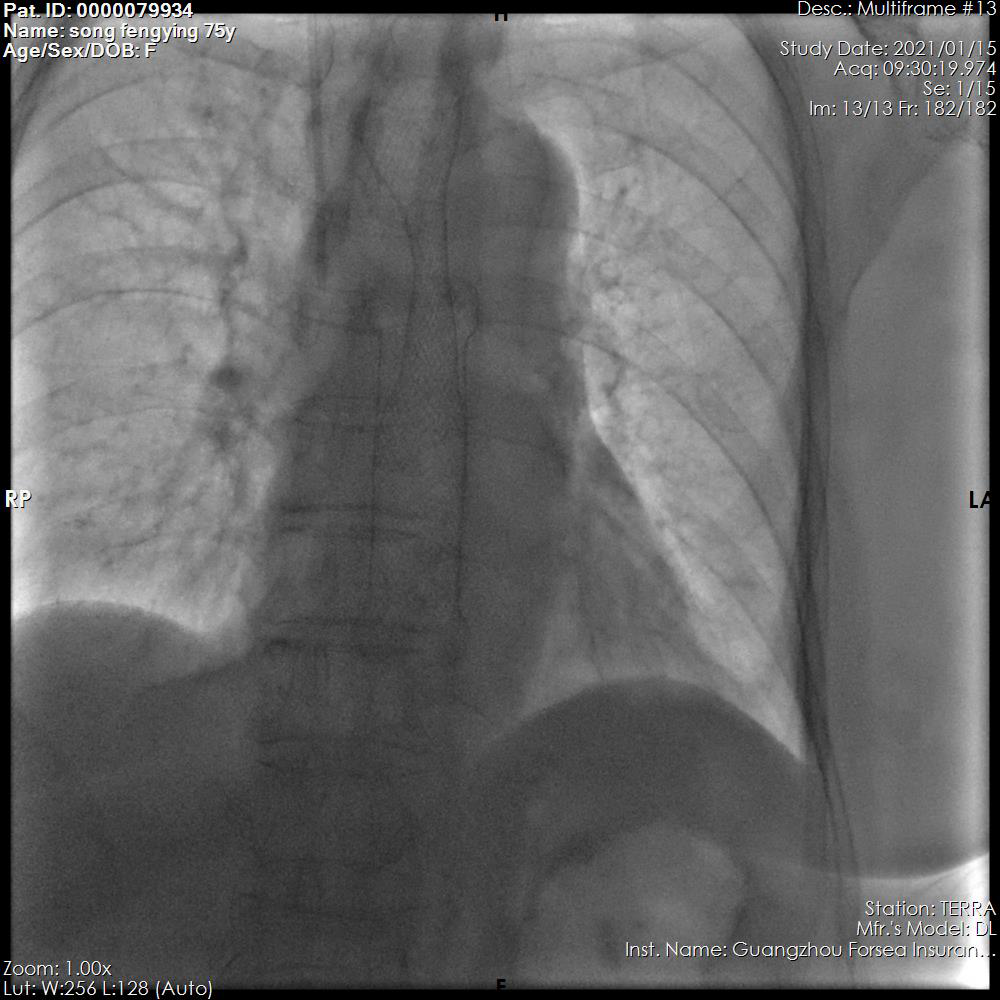

支架释放成功

晚期食管癌临床常见症状是吞咽困难,且常常由于肿瘤转移扩散,失去手术价值。通过在食管内放置支架的方法,可快速解除梗阻,恢复进食,有效改善患者生活质量及解决营养补充问题,帮助病人赢得更多的治疗机会和生存时间。